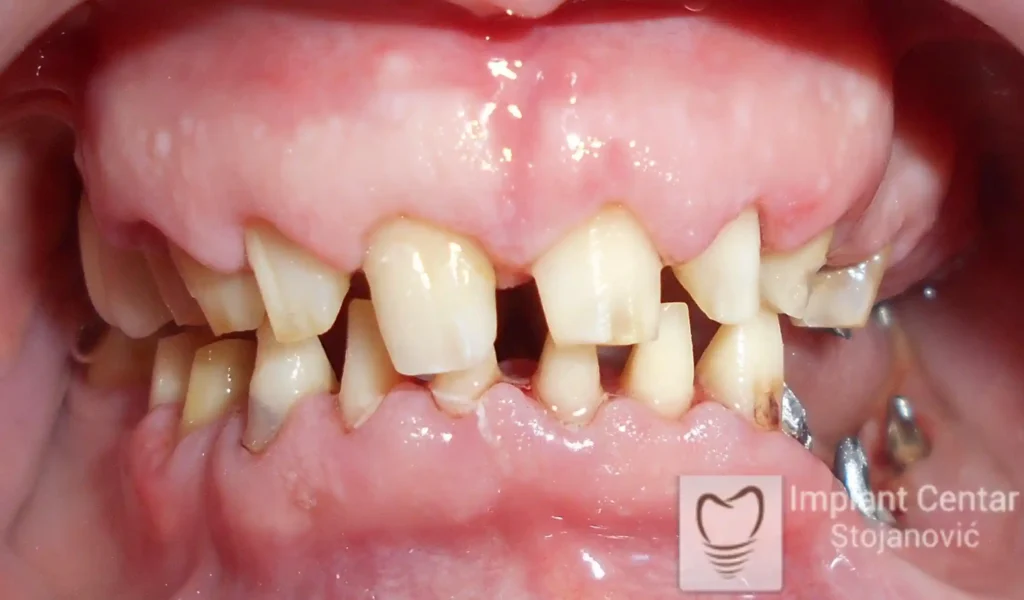

Na slikama 1, 2, 3 , 4  i  5 prikazan je izgled pacijenta pre početka terapije. Nakon detaljne kliničke i radiološke analize, doneta je odluka o vađenju zuba loše biološke vrednosti, dok su bezuba polja sanirana ugradnjom dentalnih implantata.

Nakon ugradnje implantata i pripreme preostalih zuba, pacijentu su izrađene fiksne privremene krunice, čime je postignut eugnatan zagriz već nakon jednog dana (slika 8, 9 i 10). Tokom perioda osteointegracije, pacijent se postepeno privikavao na novi položaj vilica i zagriz.

Po završetku perioda integracije, izrađeni su definitivni cirkonijum-keramički mostovi, čime je postignuta potpuna rekonstrukcija zagriza, kao i značajno poboljšanje estetike i oralne funkcije (slika 12, 13, 14 i 15).